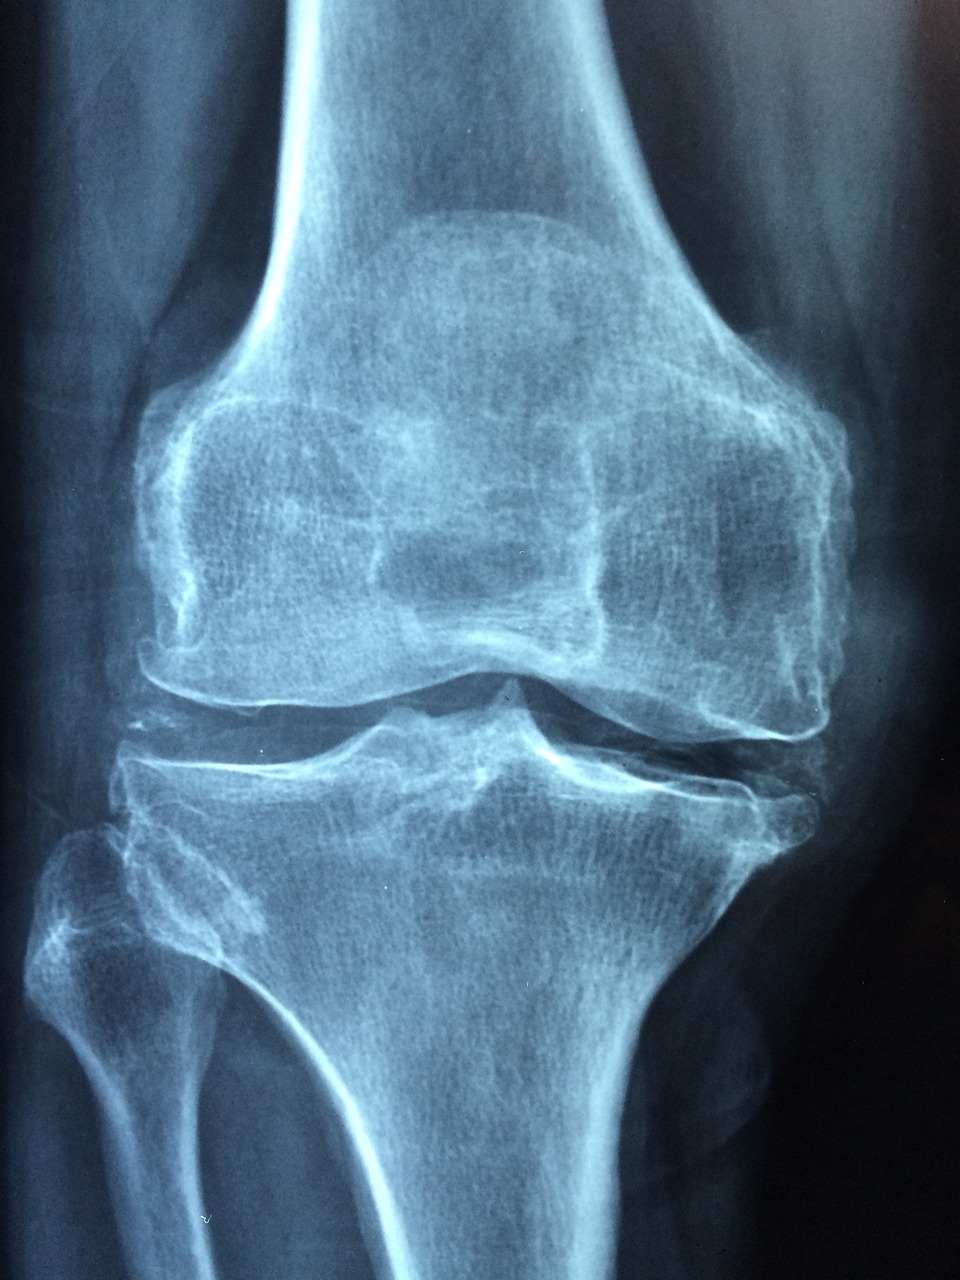

- 포스트로어티브 관절 통증: 골다공증으로 인해 뼈가 약해지면 관절 근처의 통증이 발생할 수 있습니다. 이는 흔히 무릎 및 골반 관절에 영향을 미칩니다.

- 뼈의 쉬운 파골 또는 골절: 골다공증으로 인해 뼈의 밀도와 강도가 감소하므로 일상적인 활동으로도 뼈가 파골되거나 골절할 수 있습니다. 특히 손목, 고관절, 골반 부위에서 자주 나타납니다.